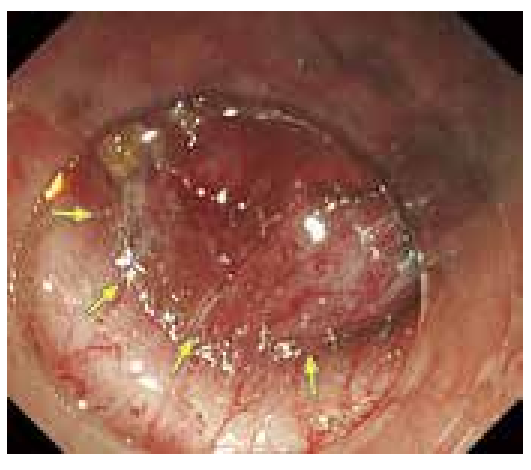

在黏膜下层发现了比较严重的血管增生及纤维化,考虑肿瘤有可能浸润至黏膜下层。

尽可能暴露透明的黏膜下层,紧贴固有肌层上方进行仔细剥离,对丰富的血管进行凝固止血。

图片右侧为口侧。在黏膜平缓隆起的中央,观察到不规则的发红凹陷。

NBI下放大观察到的R型微细血管从表层到深处,在组织学上显示逐渐变粗的倾向。